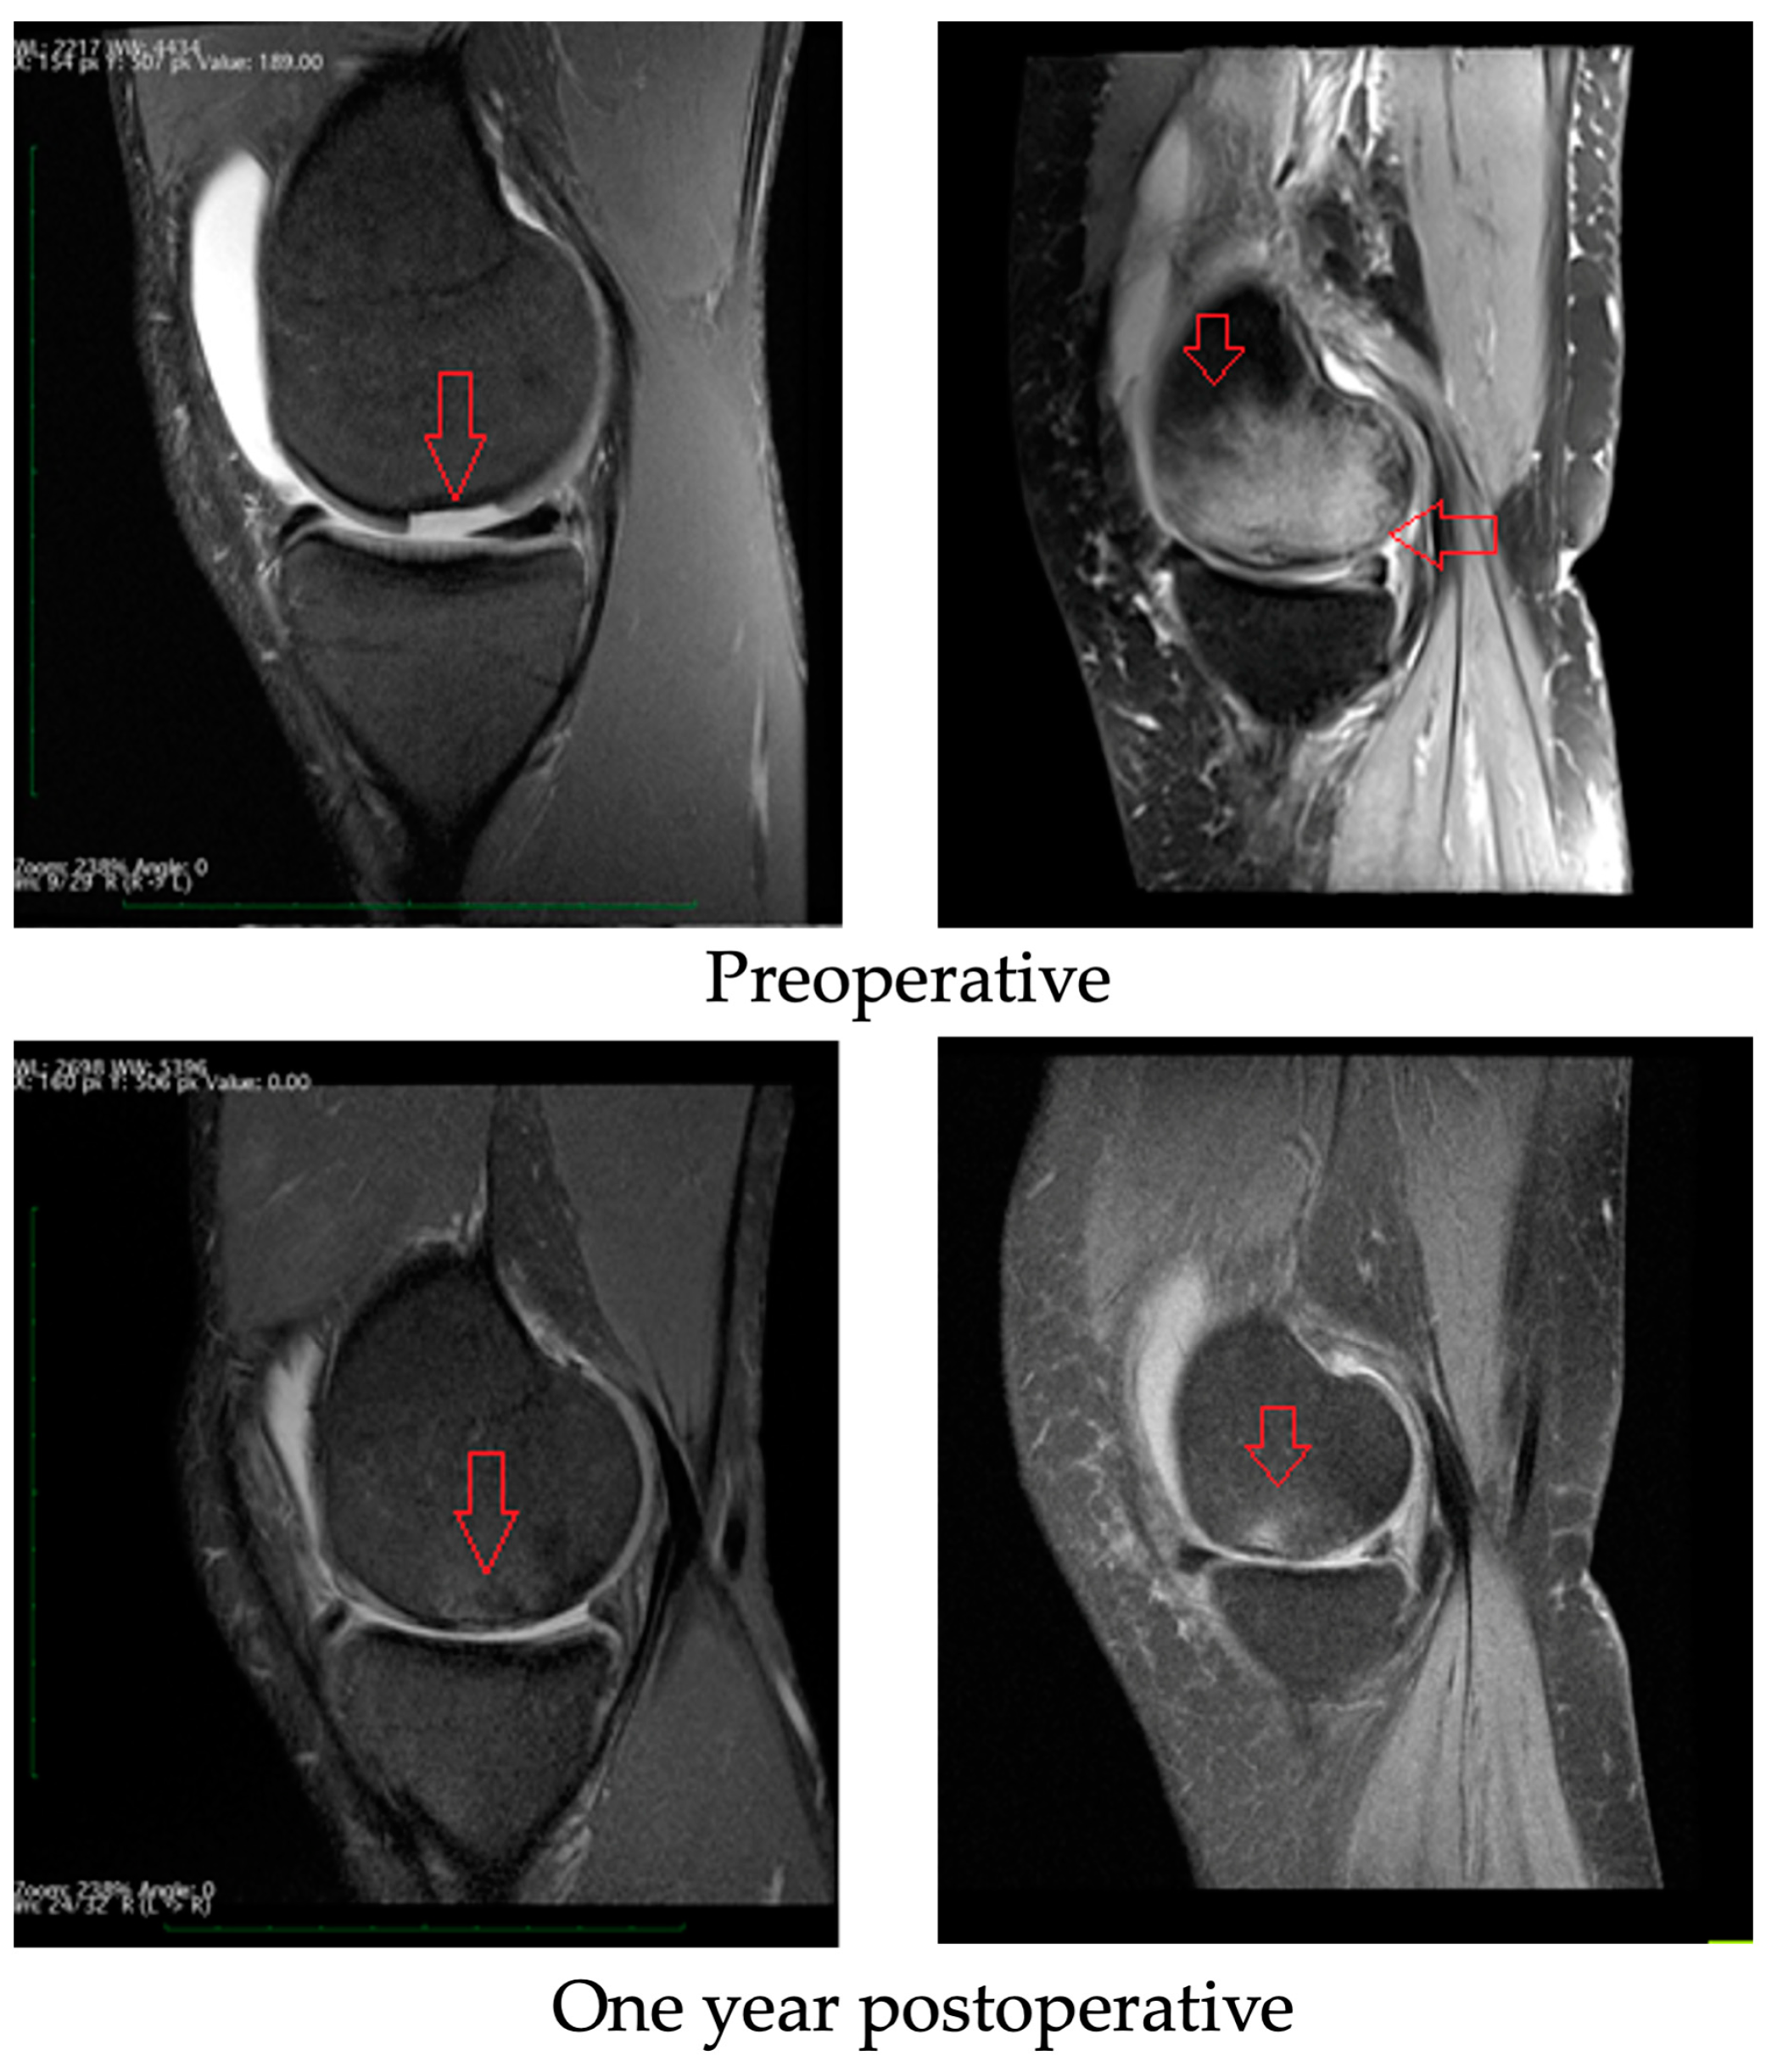

3.3. Radiological Evaluation

All patients underwent a postoperative SIGNA 1.5T HDx MRI scan. Similar results were obtained for all groups of athletes included in this study. An example of the results is shown in Figure 6. Comparing the pre- and postoperative MRI scans, it is noted that the periosteal inflammatory reaction and bone marrow oedema resolved, and the cartilage defects were filled with new tissue. Before the operation, fluid could be seen in the supraspinatus lobe (which is the result of damage and overloading of the knee). After surgery, the fluid began to be absorbed and did not recur after exercise. The oedema of the subchondral layer (visible in the form of light-colored bone) retreated (dark-colored bone one year after surgery), indicating that the wound was healing.

Figure 6.

MRI findings: preoperative and one year postoperative. Red arrows for preoperative images show cartilage damage with ICRS grade IV loss (image on the left) and marrow oedema as a result of cartilage damage and lack of treatment (image on the right) and for one year postoperative images red arrows show evolution of cartilage healing (image on the left) and withdrawal of oedema from bone (image on the right).